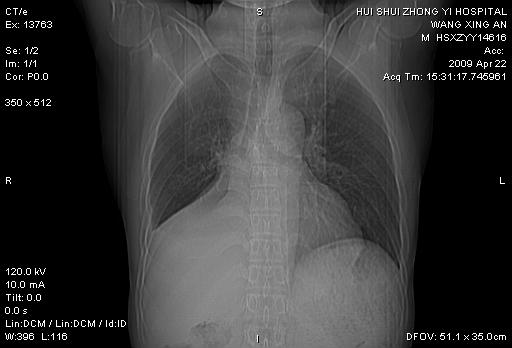

标题: CT19534:患者男、46岁咳嗽、胸痛半月。 [打印本页]

标题: CT19534:患者男、46岁咳嗽、胸痛半月。

中央型肺癌,右侧腹水

右侧中心性肺癌并下叶肺不张,双肺及纵隔淋巴结转移,右侧胸腔积液

右下肺中央型肺癌并右肺转移,右肺不张,右侧胸腔积液。

1、右下肺中央型肺癌并右肺转移,右肺下叶不张。(肿块围绕右肺下叶支气管生长,致管腔闭塞右肺下叶不张;右肺有结节影)。

2、右侧胸腔积液。

3、右中上肺陈旧性肺结核(右肺见纤维化病灶及点状钙化)。

1。右下肺中央型肺癌并肺转移,右肺下叶不张。(两肺都有结节影)。

1)右肺中间段支气管癌并右肺下叶肺不张。2)右肺上叶、两肺下叶背段感染性病变。3)右侧少量胸腔积液。